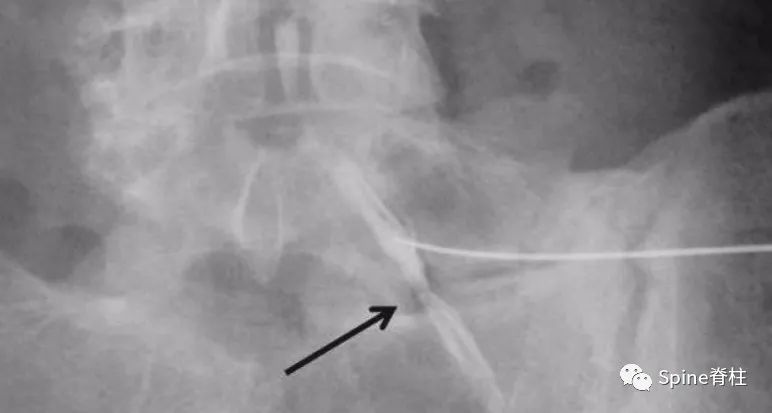

为了阐述这个问题,我们需详知脊神经的走行。 以L5神经根为例 ,L5神经除了在入口根、走行根或出口根处受椎间盘影响外,也可在远离椎间孔区域,受L5椎体侧缘骨赘压迫,或在L5肥大的横突与骶翼之间受压迫,引起典型的L5神经根病,从而出现与腰椎间盘突出症相似的下肢放射痛,也有学者称之为远端综合征。然而,L4-S3脊神经出椎间孔后逐渐汇成骶丛,而后形成坐骨神经(sciatic nerve),如果坐骨神经受损则同样会出现类似于腰椎间盘突出症的下肢放射痛。临床中,坐骨神经常在梨状肌周围受卡压或刺激,而出现臀部及坐骨神经分布区域的疼痛或麻木等一系列综合症状,称之为梨状肌综合征(虽有争议)。

图示:脊神经的入口根(1)、走行根(2)和出口根(3)